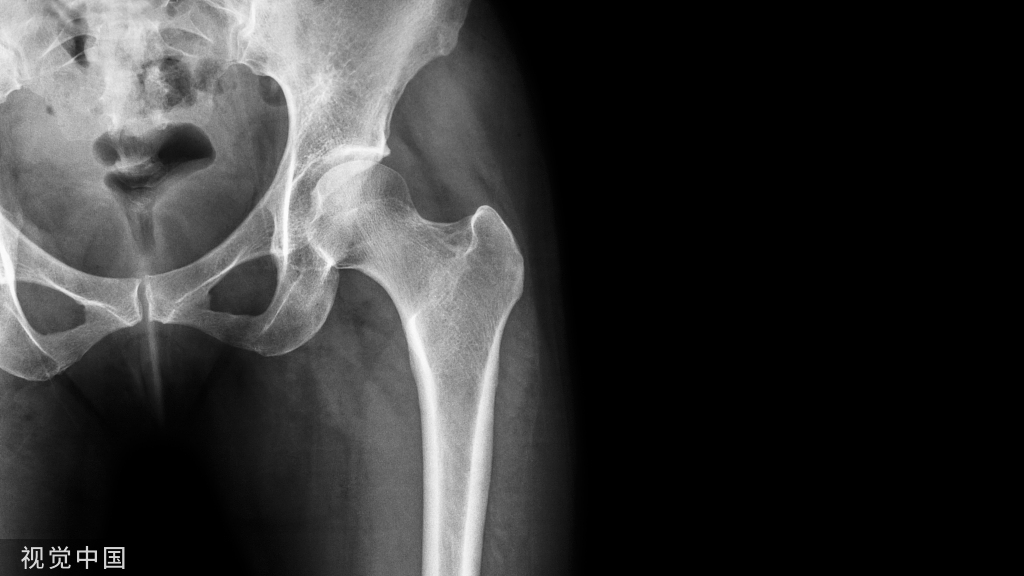

骨关节炎患者检查可见关节线压痛、关节周围骨性增加、肿胀、关节活动度减少等。X线检查如见明显的放射学表现表明已是疾病的较晚阶段,患者骨密度可表现正常,但有软骨下骨的硬化、负重部位关节间隙狭窄、软骨下骨的囊腔性改变、骨赘(也就是俗称“骨刺”)等表现。